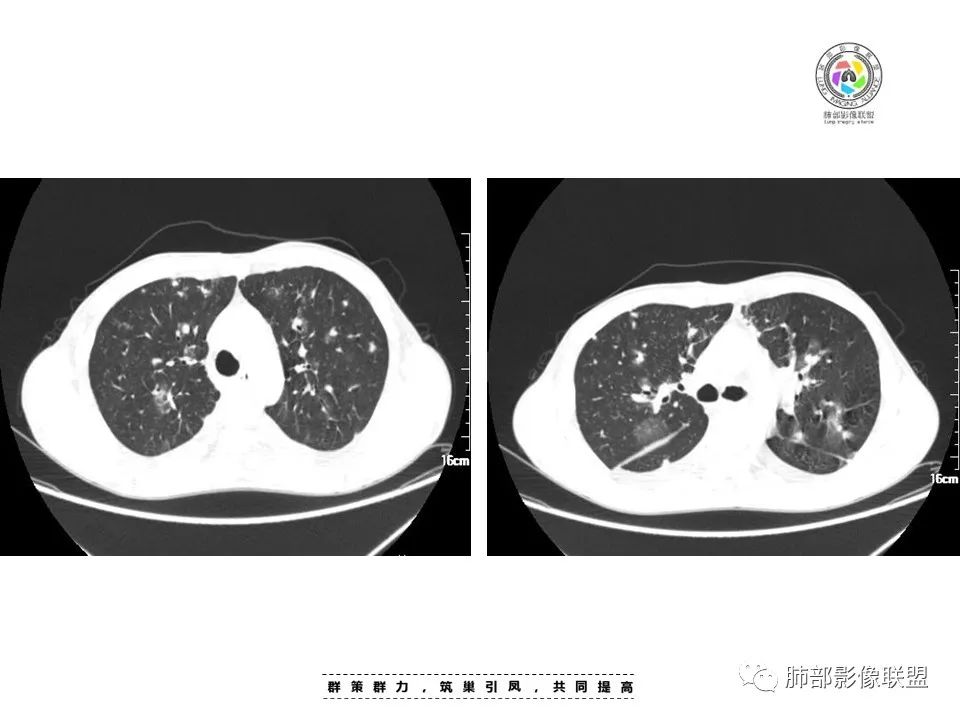

周一晚读病例:男性45岁,发热、纳差,全身散在暗紫色皮疹,结合CD4,符合HIV;肺部影像表现:两肺散在实性结节及磨玻璃密度影,实性结节伴晕征,部分沿支气管血管束分布,支气管血管束增粗,以两肺下叶为著,类似火焰征,双侧胸腔少量积液;首先考虑卡波西肉瘤,鉴别淋巴瘤增值性病变,淋巴瘤样肉芽肿/淋巴瘤,最后挂上马尔尼菲青霉菌病。

两肺弥漫性性结节状、小片状及片状带晕的病灶,煎蛋征、点晕征,主要分布两肺中下叶,病灶周围小叶间隔增厚呈网格状影,部分病灶累及胸膜,伴两侧胸膜增厚。

2.本例双肺小叶间隔增厚明显,多发结节影及片状实性密度影,沿血管支气管束分布为主,两侧较为对称,病灶多环以磨玻璃晕,边界不清。

双侧胸腔少量积液。双肺门及纵隔未见明确肿大淋巴结,纵隔结构间隙模糊。

1.结节型:两肺沿支气管血管束分布的结节影,呈火焰状或星芒状、挂果征,局部周围出血磨玻璃影(肺泡出血或水肿)。

3.肺炎渗出型:

斑片渗出影,部分融合呈“火焰样”,同时有火焰样结节,小叶间隔增厚等表现。

还可以有纵隔及腋下淋巴结增大,胸腔积液等表现。